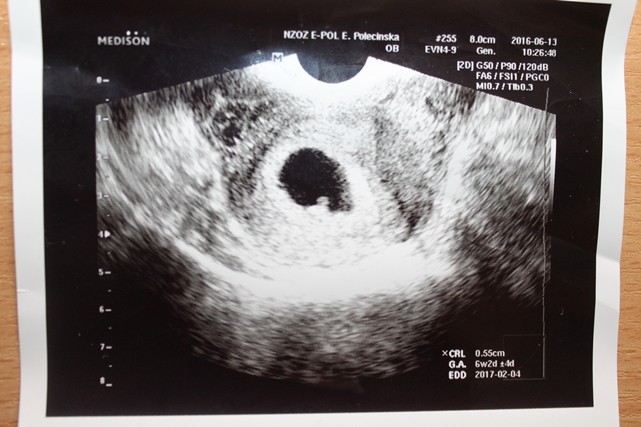

A to moje małe szczęście 6t 2dz 0.55 mm

• IMG_8222.JPG

74,9 KB · Wyświetleń: 523